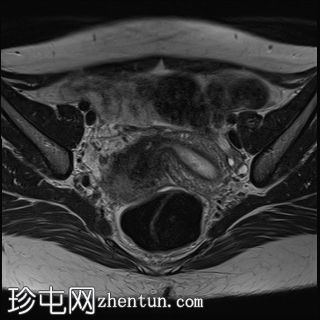

轴向位

T2

盆腔增强 MRI 检查增强了我们对 CT 扫描中发现的病变的理解。右肾发育不全,左肾肥大伴肾积水,双子宫完整,阴道隔膜,发育不全侧阴道积血。

双侧卵巢均有多个功能性囊肿,右侧卵巢可见黄体囊肿。

道格拉斯囊内可见少量游离液体。

CT和MRI检查结果为Herlyn-Werner-Wunderlich综合征的典型表现,其特征为经典的三联征:III型苗勒氏管异常(完全性双子宫)、中肾管异常(肾发育不全)以及肾发育不全侧阴道积血。